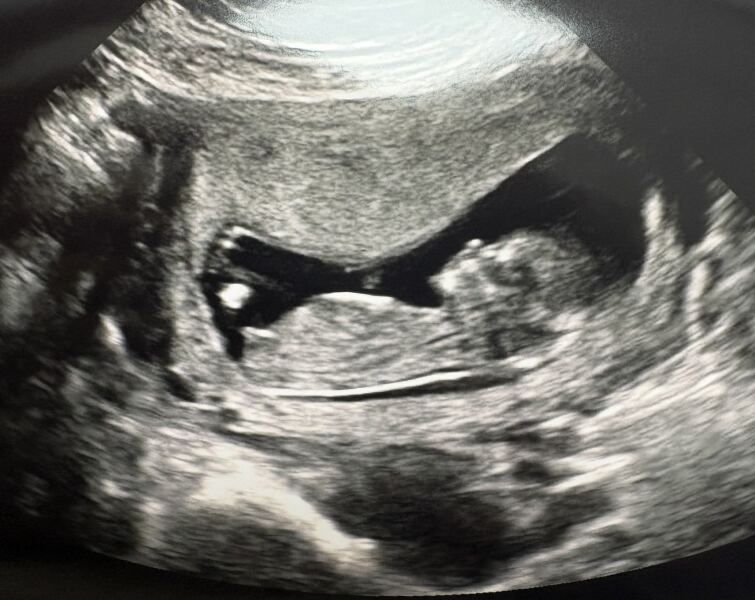

Has anyone used early glimpse for a gender prediction based on nub theory and it been right? I got this from them and really hoping it’s right! 🤞🏻I have included the original scan and a couple others I have too.

Nub theory - early glimpse